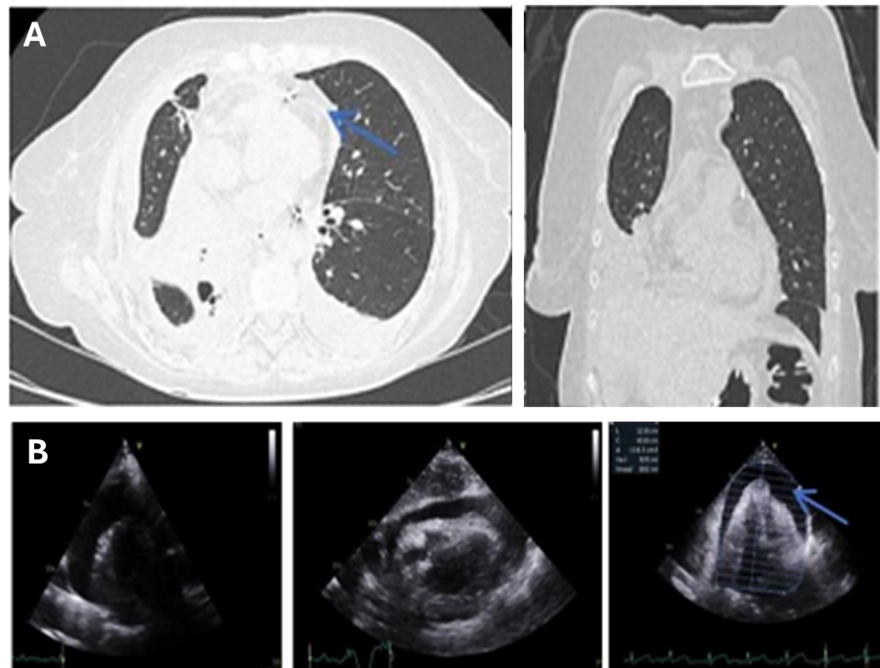

Extensive Left Ventricular Thrombosis in a Young Patient: An Unexpected Threat

Humberto Morais, Tshimbalanga Merite, Miguel Vicente, Capela Pascoal, Mauer Alexandre da Ascensão Gonçalves